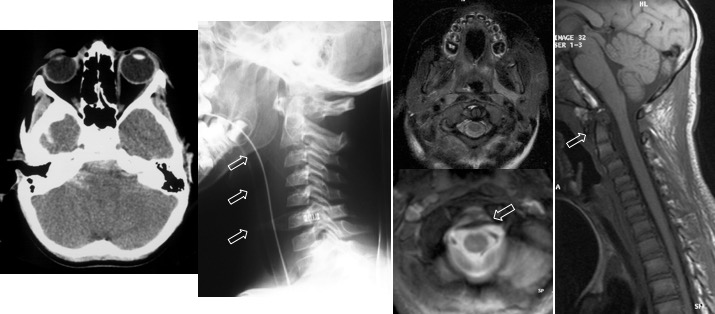

ces lésions étaient considérées classiquement comme hautement instables, rarement retrouvée chez les patients vivants mais plus souvent lors d’autopsie de traumatismes à haute cinétique (AVP Cf. ci-contre).

il peut exister une déchirure durale qui provoque la formation d’une méningocèle rétro-oesophagienne.

depuis l’utilisation large de l’IRM, on a noté qu’en fait les lésions traumatiques occipito-C1 non déplacées ne sont pas si exceptionnelles. il faut y penser devant une hémorragie sous-arachnoïdienne du bas de la fosse postérieure. Le traitement de ces cas est orthopédique.